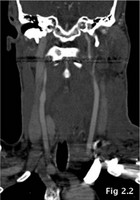

A contrast-enhanced CT-scan of the head and neck was performed. This showed complete laceration of the left lobe of the thyroid gland, which was transected into an upper and a lower portion. No contrast extravasation - a sign of active bleeding - was present at this time. The left superior thyroid artery was not injured and perfusion of the upper fragment of the left split thyroid gland was intact.

The situation was similar in the lower fragment, which was fed by the inferior thyroid artery (Fig. 2).The larynx and trachea did not show any abnormalities.